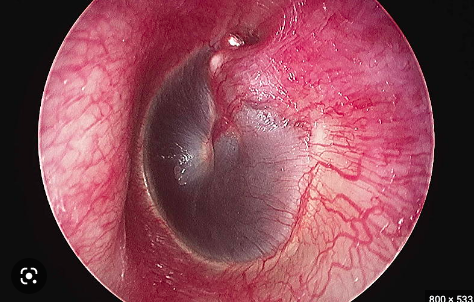

What is the name for this basal skull fracture sign? [1]

Hemotympanum